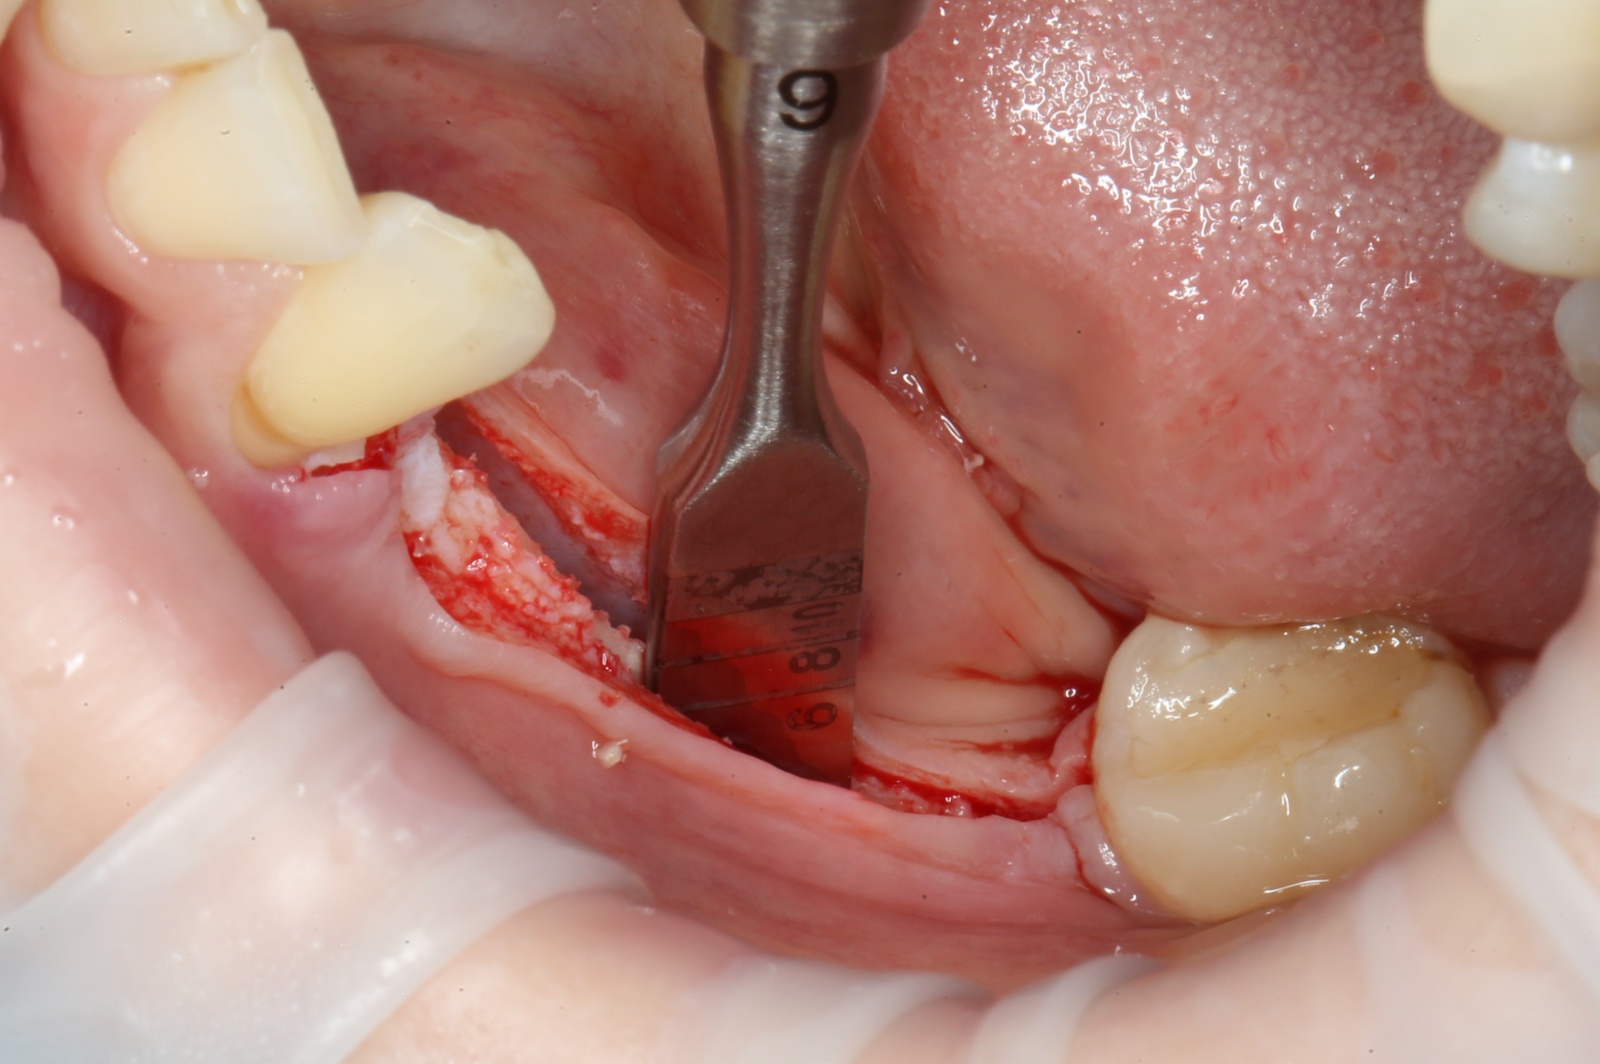

Скелетирование:

Ультразвуковой наконечник располагается перпендикулярно кости, вследствие чего формируется «траншея» вдоль того участка, где отсутствуют зубы. Глубина этой траншеи составляет 10 мм.